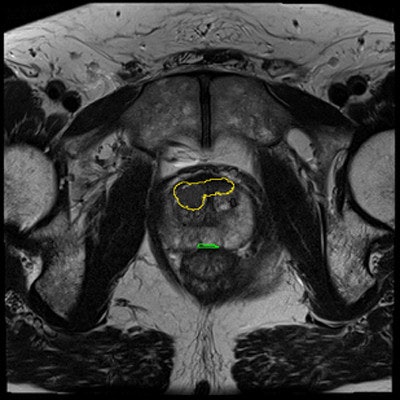

Henkjan Huisman, PhD, assistant professor of radiology at the diagnostic image analysis group at the department of radiology, Radboud University Medical Center.Something better still is needed, and that is prostate cancer CAD. A few years ago PhD student Geert Litjens, Huisman, and colleagues developed a fairly simple but functional prostate cancer CAD that performed "pretty well," Litjens said. The group has since updated it, expanding it to include zonal registration of tumors and multiatlas reference capabilities. There is feature extraction that looks for quality and texture features and a voxel classifier for tumor candidate detection and segmentation as well.

The CAD works in two stages: voxel classification and a subsequent candidate segmentation and classification stage, he noted. CAD features include quantified T2 measures, apparent diffusion coefficient (ADC), pharmacokinetics, texture, and anatomic characteristics. Both receiver operating curve (ROC) and free-response ROC (FROC) were used for analysis.

The results in 130 patients showed high sensitivity at a low false-positive rate. CAD performed at about the level of radiologists, and it provides complementary information so that combined, the result is significantly better, according to Litjens.

Prostate CAD scheme shows high detection rate, and results can be improved when CAD is used as a second reader. In 130 prostate cancer patients, CAD and radiologists were shown to have similar sensitivity. Simulating the addition of CAD improved sensitivity from 0.78 to 0.87 (indolent versus aggressive tumors). It improved sensitivity from 93% to 98% at PI-RADS 4.For aggressive cancers at PI-RADS levels four and five, "we able to show that CAD improves the area under the curve from 0.78 to 0.87," Huisman said. "If a radiologist were to use CAD, then the sensitivity would increase 98%, which would really allow them to not do any biopsies for PI-RADS, which is clinically very relevant."